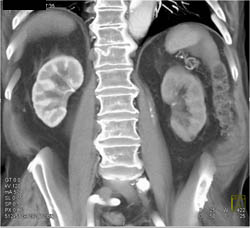

Right Nephrectomy Bed